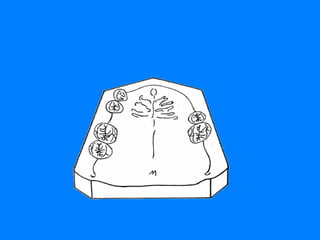

CLASE I LIMITACION 14-24   DOBLE EFECTO DE ARCO CRUZADO REBORDES RESIDUALES Y PALADAR EFECTO DE ARCO CRUZADO MUCOSO CLASE I LIMITACION 34-44 DOBLE EFECTO DE ARCO  CRUZADO REBORDES RESIDUALES

EFECTO DE ARCO  CRUZADO MUCOSO ESTE SE LIMITA UNICAMENTE A LA POSIBILIDAD QUE PUEDEN BRINDAR EL PALADAR Y LOS REBORDES RESIDUALES ( ARCO MAXILAR )  Y  ( ARCO MANDIBULAR ) DE COLABORAR EN LAS FUNCIONES DE SOPORTE Y ESTABILIDAD, YA QUE LA FUNCION DE RETENCION EVITANDO EL DESALOJO DE LA RESTAURACION PARCIAL REMOVIBLE ES UNA FUNCION  BASICA   DE LOS DIENTES PILARES.